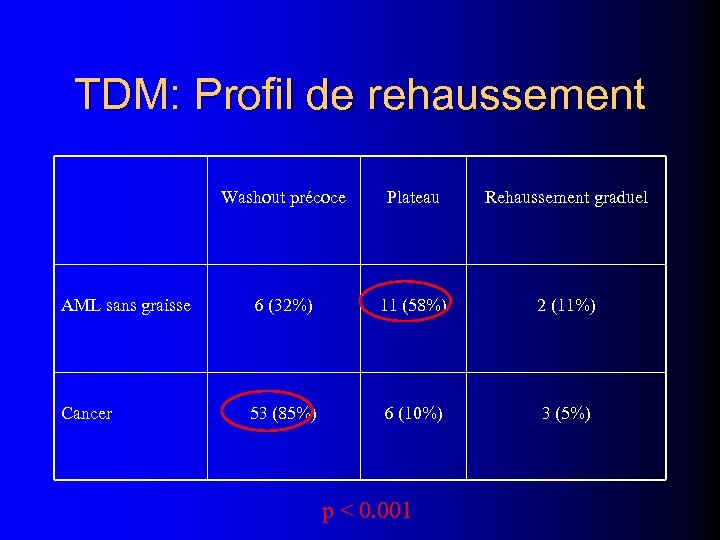

TDM: Profil de rehaussement Washout précoce Plateau Rehaussement graduel AML sans graisse 6 (32%) 11 (58%) 2 (11%) Cancer 53 (85%) 6 (10%) 3 (5%) p < 0. 001

TDM: Profil de rehaussement Washout précoce Plateau Rehaussement graduel AML sans graisse 6 (32%) 11 (58%) 2 (11%) Cancer 53 (85%) 6 (10%) 3 (5%) p < 0. 001